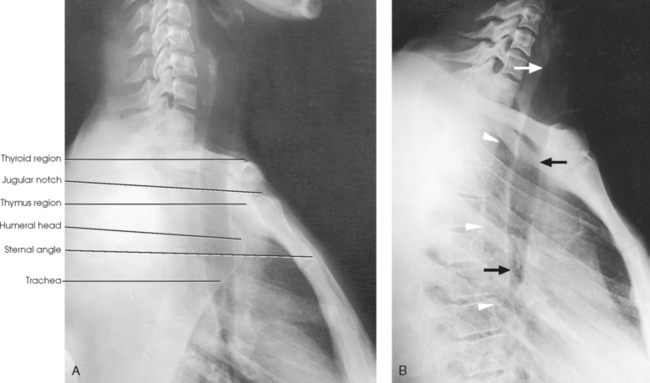

Structures shown: A lateral projection shows the air-filled trachea and the regions of the thyroid and thymus glands. This projection, first described by Eiselberg and Sgalitzer,1 is used extensively to show retrosternal extensions of the thyroid gland, thymic enlargement in infants (in the recumbent position), and the opacified pharynx and upper esophagus and an outline of the trachea and bronchi. It is also used to locate foreign bodies.